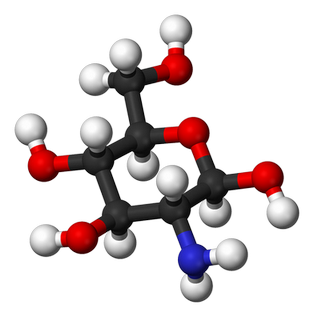

Глюкозаміну гідрохлорид

Нормалізує утворення внутрішньосуглобової рідини, зменшує вираженість неприємних відчуттів у суглобах, покращує їх рухливість. Cприяє відновленню хрящової тканини

02